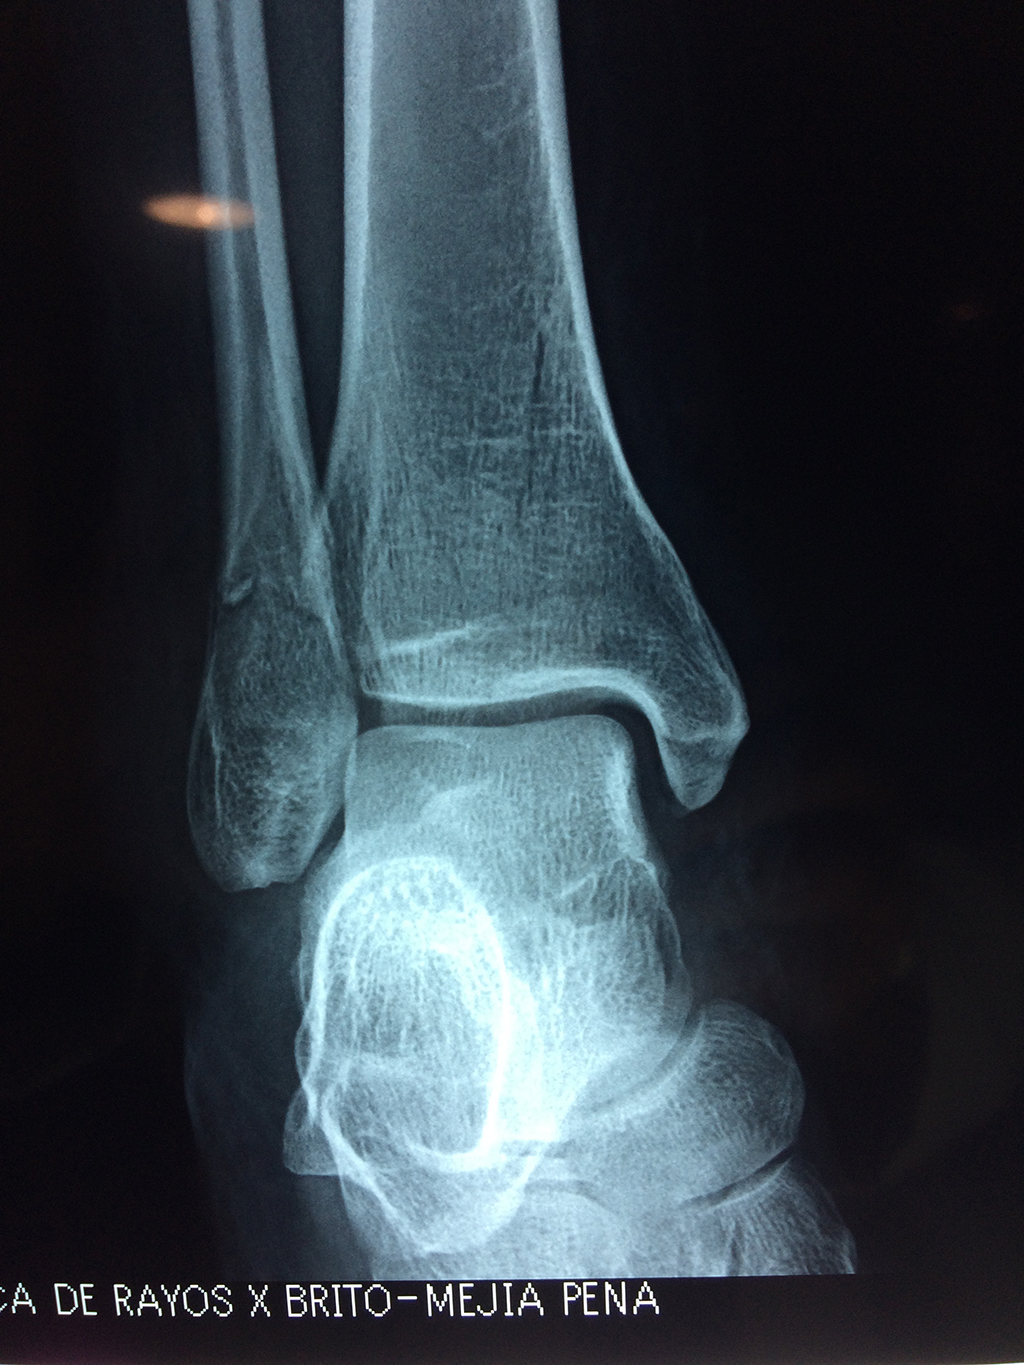

Una fractura de tobillo es la rotura de uno o más de los huesos del tobillo. Estas fracturas pueden ser:

Algunas fracturas de tobillo pueden requerir cirugía si:

- Los extremos de los huesos están desalineados entre sí (desplazados).

- La fractura se extiende hasta la articulación del tobillo (fractura intra-articular).